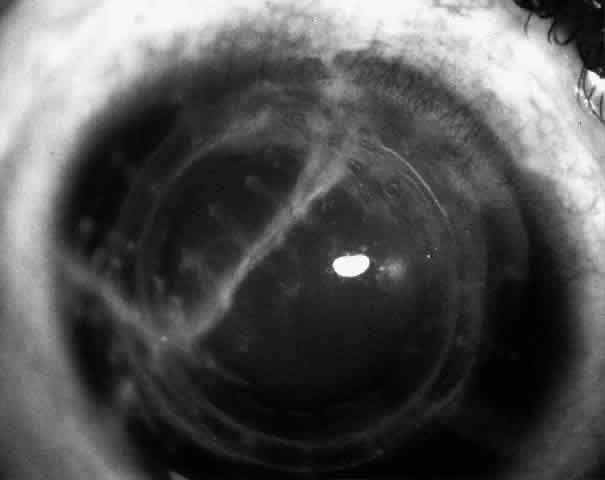

Bowman's layer in the tissue lens seems to undergo some deterioration if the surface is not covered by epithelium within 7 to 10 days.14 Therefore, if an epithelial defect persists beyond this period (Fig. 15), it is worth considering removing the lenticule and replacing it with a different lenticule when the eye is no longer irritated.

Fig. 15. A persistent epithelial defect in a lenticule being removed because of failure to epithelialize.